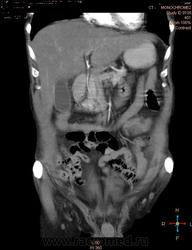

Здравствуйте, коллеги.Помогите разобраться.Пациент 1949 г беспокоять боли в животе , отсутствие аппетита, похудание .За неделю пожелтел, ослаблен.Нужно исключит кацер головки подж.железы.Анализы сегодня сдал еще не готовы.УЗИ зак увеличение л\узлов у ворот печени.Образов головки подж.железы ?На КТ жировой гепатоз.вроде головка подж железы не увеличены.

Мне надо исключить или поставить образование головки подж.железы.Хирурги ждут заключение, хотять оперировать.

А про билиарную гипертензию на УЗИ и КТ ничего не говорится?

Даже если вы пропустили малый рак панкреас, пациент умер не из-за него - желтуха не механическая, а, вероятней, паренхиматозная.